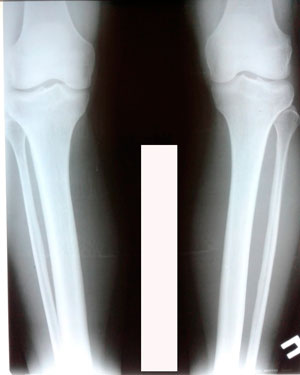

Исходник - 33 года. Бишкек

Дата операции 19.03.2020

перед крутками